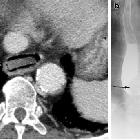

pierced in the upper esophagus.Left image during swallowing contrast medium, right image after swallow only dimly visible.

und im oberen Ösophagus steckengebliebener Hühnerknochen in der Breischluckuntersuchung als schräg liegende Kontrastmittelaussparung zu erkennen.